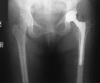

Background: Offset in THA correlates to abductor muscle function, wear, and impingement. Femoral offset after THA is not independent of the cup center of rotation (COR) so hip offset, a combination of femoral offset and change in hip COR, becomes the important measurement.

Methods: We compared hip offset of arthritic and contralateral normal hips on radiographs in 82 patients (82 hips) who had THA. We used computer navigation in all patients with the aim of reconstructing the hip offset and to compare hip offset change to the quantitative change of the hip COR.

Results: The preoperative radiographic change to equalize the offset ranged from -12 to +21 mm (mean, 1.5); postoperatively the change was 1.4 ± 6.4 mm and was within ± 6 mm in 78 of 82 hips. As COR displaced superiorly from 3 to 6+ mm the offset had to be substantially increased. Only with COR 0-3 mm superior and 0-5 mm medial was offset always within 5 mm.

Conclusions: Hip offset reconstruction was directly related to the position of the hip COR, and navigation allowed quantitative control of offset and hip length.